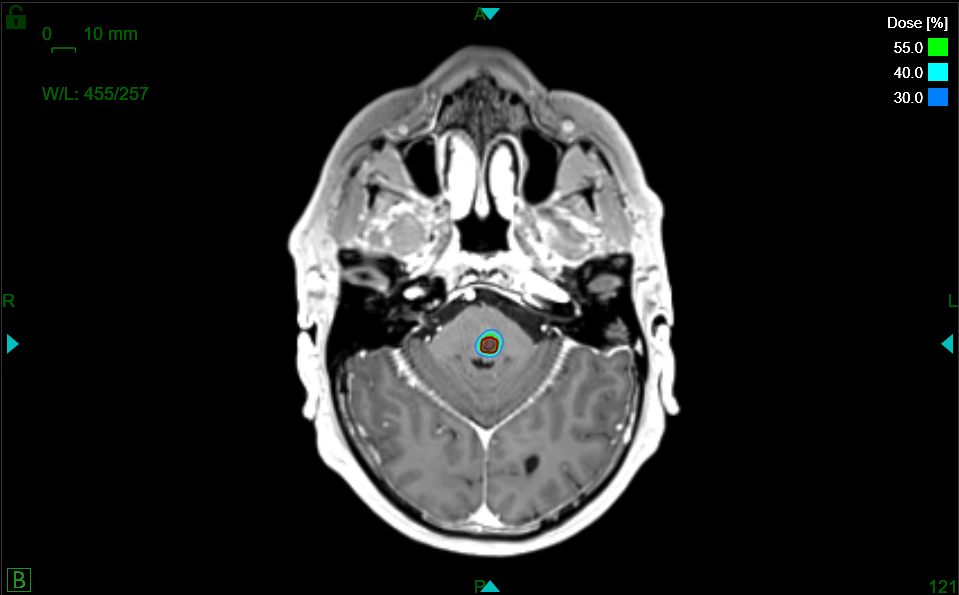

Schnell kommt die Frage nach möglichen Behandlungsformen auf. Eine Option ist die hochpräzise Radiochirurgie, welche die SNRC AG in Zürich auf dem neusten Stand der Technik mit dem ZAP-X® anbietet. Diese Form bietet den Betroffenen eine Alternative bzw. Ergänzung zur klassischen Operation oder der herkömmlichen, meist langwierigen Strahlentherapie.

Mit dem ZAP-X können Tumore, Metastasen und auch Krankheitsbilder wie Trigeminusneuralgie hochpräzise, effektiv, nachhaltig und bei gleichzeitiger Schonung des umliegenden, gesunden Gewebes therapiert werden. Die Behandlung erfolgt ambulant und ohne Narkose. Sie dauert ca. eine Stunde, ist absolut schmerzfrei und die Patienten können im Anschluss direkt nach Hause.